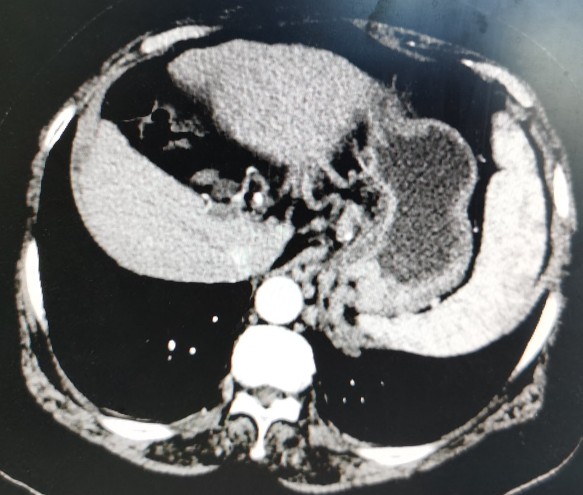

栓塞后的影像图

第一次肝动脉导管栓塞化疗术后,黄婶出现了严重的高热、腹胀和肝肾功能不全,经各种治疗后大概1周左右病情基本稳定。这次保驾护航成功以后,黄婶每次治疗都来找我,哪儿都不去,弄得我压力山大。